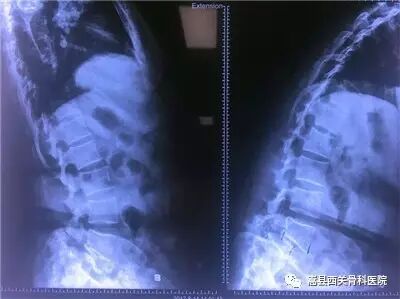

腰椎管狭窄影像资料

椎体滑脱导致椎管狭窄,术后完全复位,椎管狭窄解除!